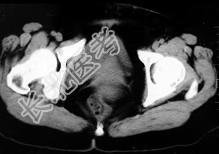

- 单项选择题女,32岁, 因停经46天,突发腹痛1天入院, 后穹隆穿刺抽出不凝血,CT检查如图所示, 下列说法错误的是 ( )

A、在左附件区可见一椭圆形略高密度病灶

B、病灶外缘较光整

C、盆腔内较高密度积液

D、此为宫外孕

E、此为卵巢巧克力囊肿